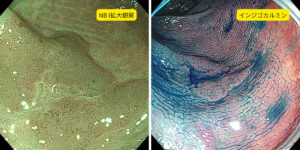

NBI観察、インジゴカルミンを散布することによって病変の境界がしっかりと認識できますね。

さらに拡大すると血管の口径は比較的整っており、均一に分布されておりいわゆるJNET Type2Aの腺腫の診断で内視鏡切除しました。

特に Narrow Band Imaging(NBI)では、粘膜表層の微細な血管構造や色調差が強調されるため、腫瘍と正常粘膜とのわずかな違いを捉えやすくなります。色調を適切に調整することで、病変の広がりや境界がより明瞭に浮かび上がり、「どこまでが病変か」を高い精度で見極めることが可能になります。

一方で、インジゴカルミン染色などの色素散布観察では、粘膜の凹凸や微細な構造が強調されるため、病変の輪郭がより立体的に把握でき、境界の同定に非常に有用です。

このように、NBIによる色調・血管の評価と、インジゴカルミン等を組み合わせることで、病変の「存在」「範囲」「性質」を多角的に評価できるようになっており、現在の内視鏡診断は極めて精度の高いものになっています。